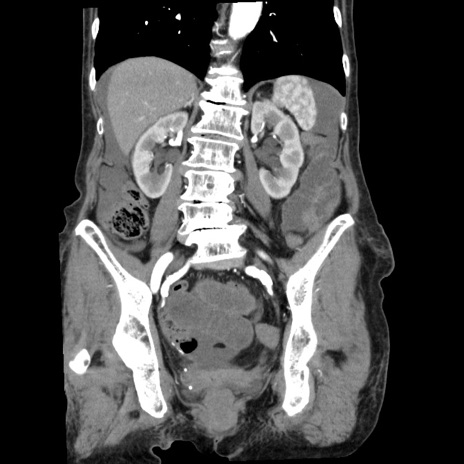

症例1(冠状断像)

【症例】80歳代女性

【主訴】腹痛

【現病歴】8時間前から腹痛あり来院。

【既往歴】糖尿病、脂質異常症、子宮体癌にて子宮全摘術

【身体所見】意識清明・会話良好だが腹痛で苦悶様、全腹部にわたって反跳痛と圧痛あり

【データ】WBC 13600、CRP 0.14、LDH 224、CK 90